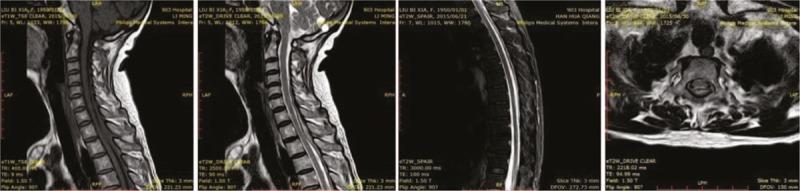

This report describes a cervical epidural abscess (CEA) caused by epidural analgesia, wherein the patient was punctured twice. A CEA was suspected based on the patient's significant neck pain and elevated white blood cell and neutrophil counts. A CEA from C6 to T8 was confirmed by magnetic resonance imaging scan.

本报告描述了一例由硬膜外镇痛引起的颈椎硬膜外脓肿(CEA),该患者接受了两次穿刺。基于患者严重的颈部疼痛以及白细胞和中性粒细胞计数升高,怀疑为CEA。磁共振成像扫描证实了从C6到T8的CEA。